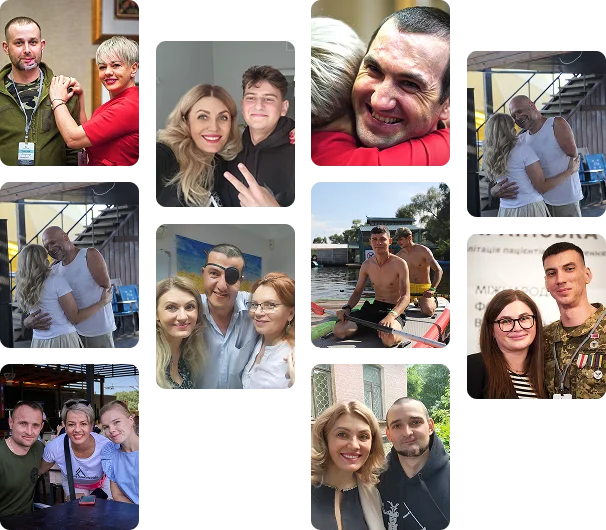

Наші пацієнти

Результати операцій

Найголовніше для нас — це усмішки наших героїв.